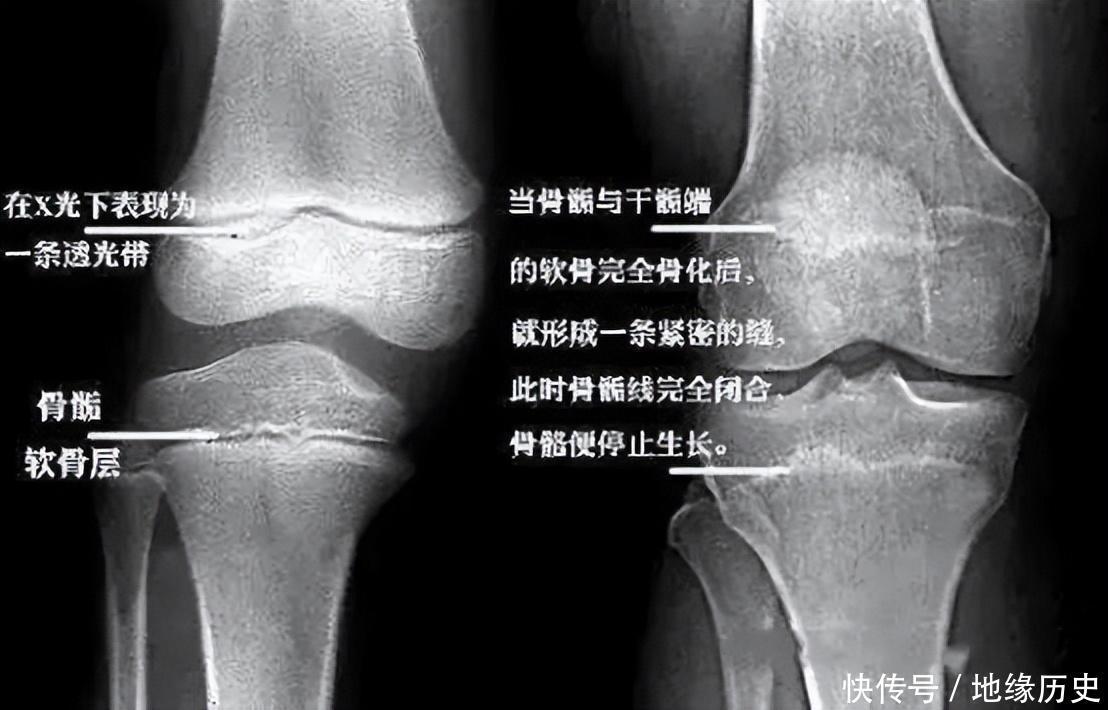

与此同期,大夫还告诉他们:“你女儿的骨头片傲气,要津缝照旧闭合上了,新2管理开户莫得再滋长发育的空间。”

听到这句话,全家东说念主倍感打击,尤其是李亚诺,他还期待着我方的大好东说念主生,何如就栽在身高上头了呢?从病院回家之后,这个男孩不言不语,将我方关在房间里不外出,自卑和低垂的心理占据了他系数的想法,以致一度连学也不想上了。